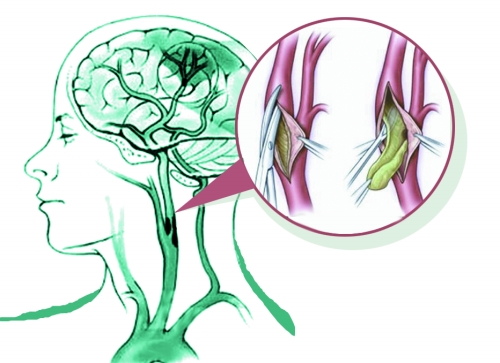

后来,老人经过进一步检查确诊,做了一侧血管的颈动脉内膜剥脱(切除)术,效果意外地好。癫痫几无再发;活动能力恢复,居然可以自己在家做刀削面(老人祖籍山西);脑子也好了,盘算着自己的工资怎样分给小孙女。所以,说明早先的问题是颈动脉狭窄引起的脑缺血造成的。

颈动脉有狭窄怎么办?严重的当然要开通。一般来说,如果有脑缺血发作的症状或者有了脑梗死,磁共振或者CT颈动脉造影显示70%或以上的狭窄、或者直接的血管造影狭窄在50%或以上,就要手术开通血管了(当然还有其他一些指证)。最经典的手术方法就是前面说过的颈动脉内膜剥脱(切除)术,现在还有微创的颈动脉支架植入术。各种手术方法都是有各自的适应证的。

颈动脉内膜剥脱